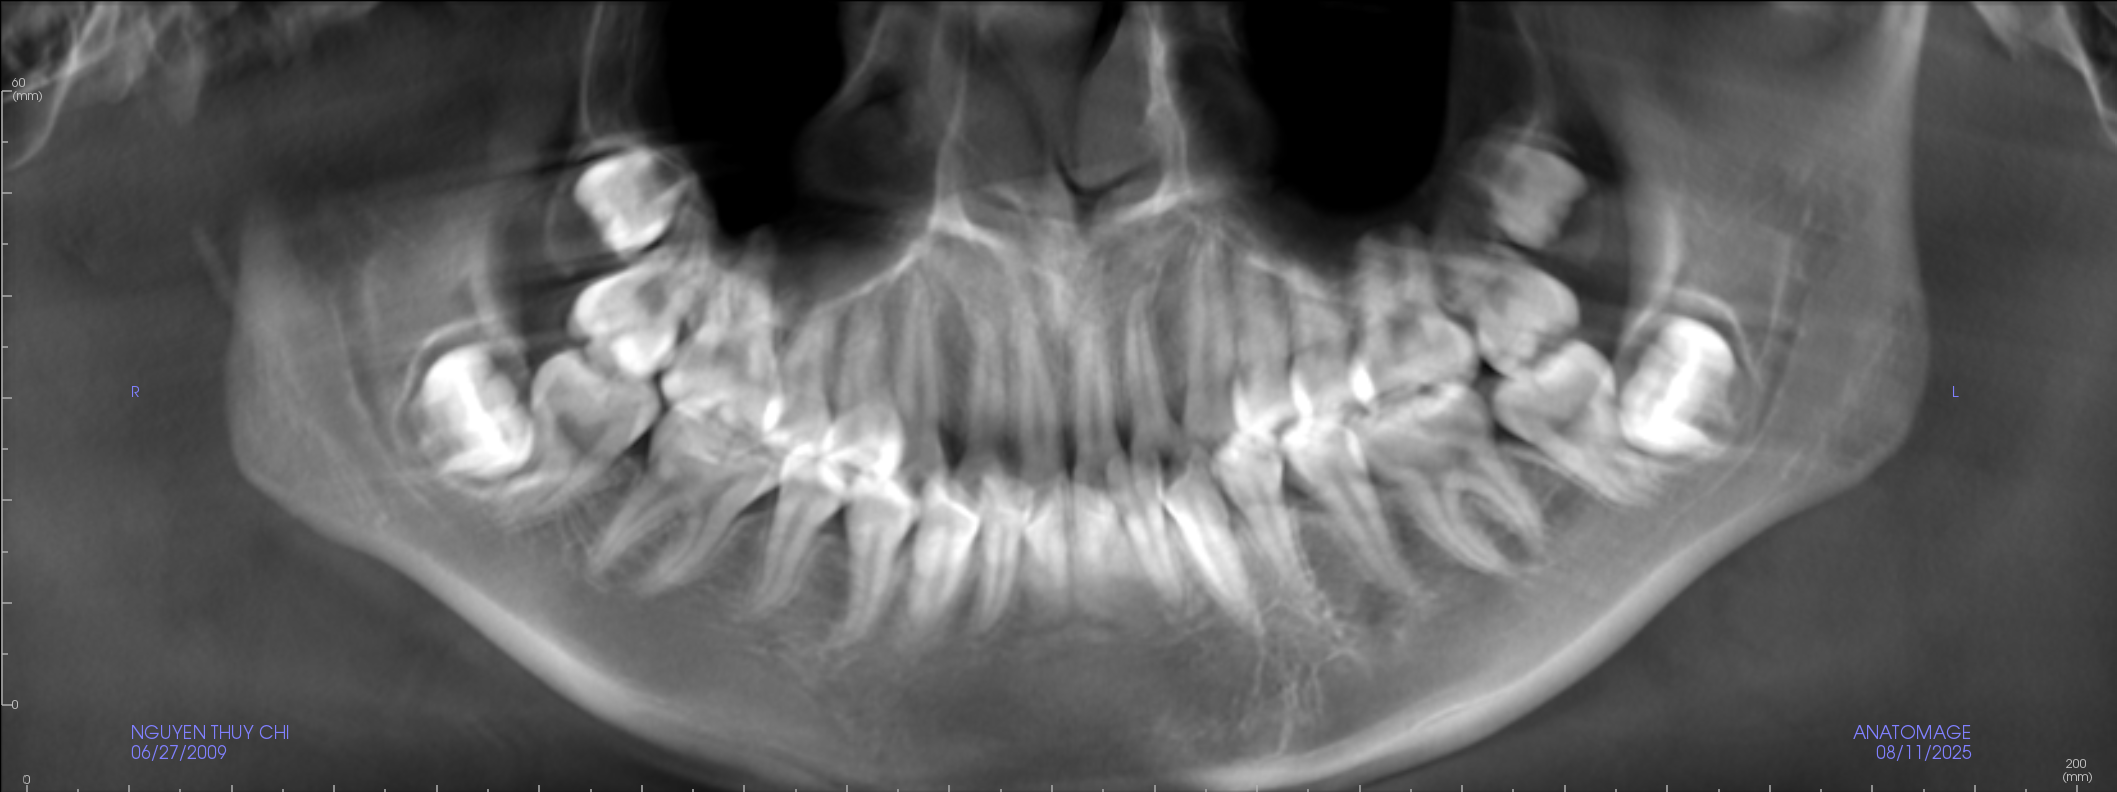

Bước 3: Chụp phim X

Tùy thuộc vào tình trạng răng miệng của bạn và chỉ định của nha sĩ, bạn có thể cần phải chụp phim X – quang hoặc thực hiện các xét nghiệm khác như xét nghiệm nướu hoặc xét nghiệm gen để kiểm tra kỹ lưỡng hơn.

Nên khám răng định kỳ bao lâu một lần? Giải thích đầy đủ 4

Chụp X-quang răng để chẩn đoán chính xác